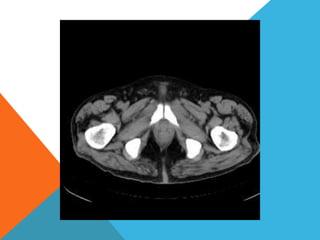

El paciente presentó síntomas de sangrado digestivo y pérdida de peso. Exámenes revelaron gastritis crónica asociada a H. pylori. Un tumor fue descubierto en una colonoscopia normal. La cirugía removió un tumor fibroide solitario, una rara neoplasia mesenquimal que usualmente crece lento y tiene bajo potencial de malignidad. El pronóstico después de la remoción quirúrgica es generalmente bueno.